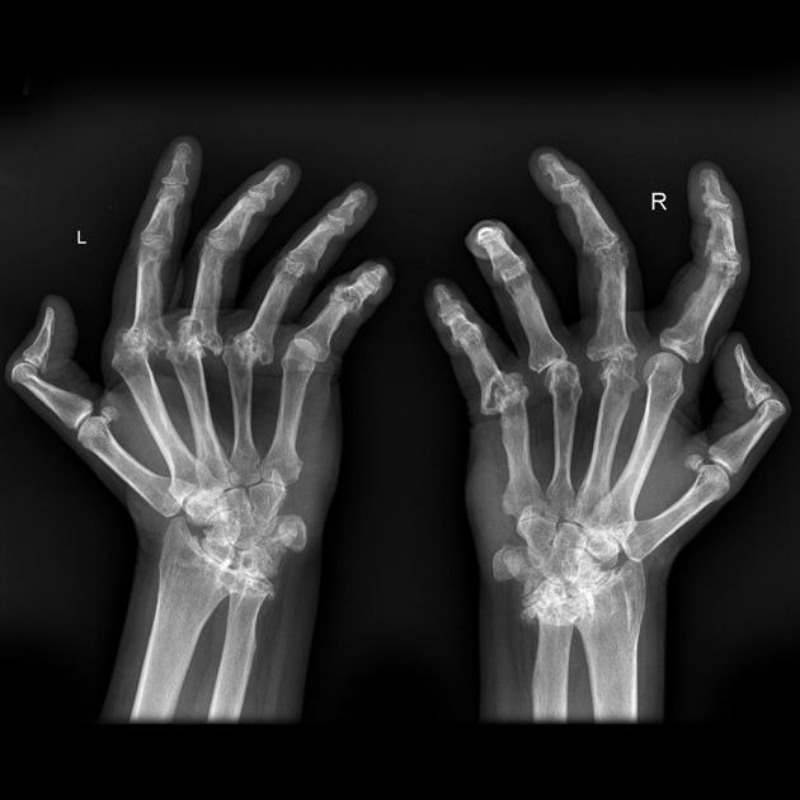

Hình ảnh X-quang viêm khớp dạng thấp

Chụp X-quang cho thấy hình ảnh bệnh từ bên trong đồng thời kiểm tra những tổn thương, biến chứng viêm khớp dạng thấp nghiêm trọng của bệnh. Bạn có thể tham khảo một số mẫu ảnh chụp X-quang ở nhiều bộ phận của các bệnh nhân viêm khớp dạng thấp.

Biến dạng khớp ngón tay trên xquang

Những biến dạng khớp bàn tay của bệnh nhân bị viêm khớp dạng thấp, đặc biệt rõ rệt ở các khớp bàn – ngón tay. Ảnh: Radiopaedia